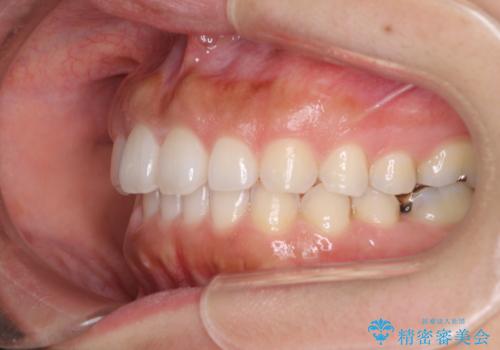

隙間の空いた前歯を閉じたい インビザライン矯正

- 前歯の隙間を気にして来院された患者様です。

隙間、捻転ともに軽微でありましたが、下顎前歯の突き上げにより隙間ができていたため、インビザラインを用いて咬み合わせを改善しながら前歯の歯列を整えていくこととしました。

当初は1年程度で終えられると思いましたが、治療途中から装着時間が短くなったり、来院間隔が長期になったりとし、結果として4年半以上の治療期間となりました。

治療途中に上顎前歯は失活してしまいましたが、変色が顕著ではないため、経過を見ていくこととなりました。